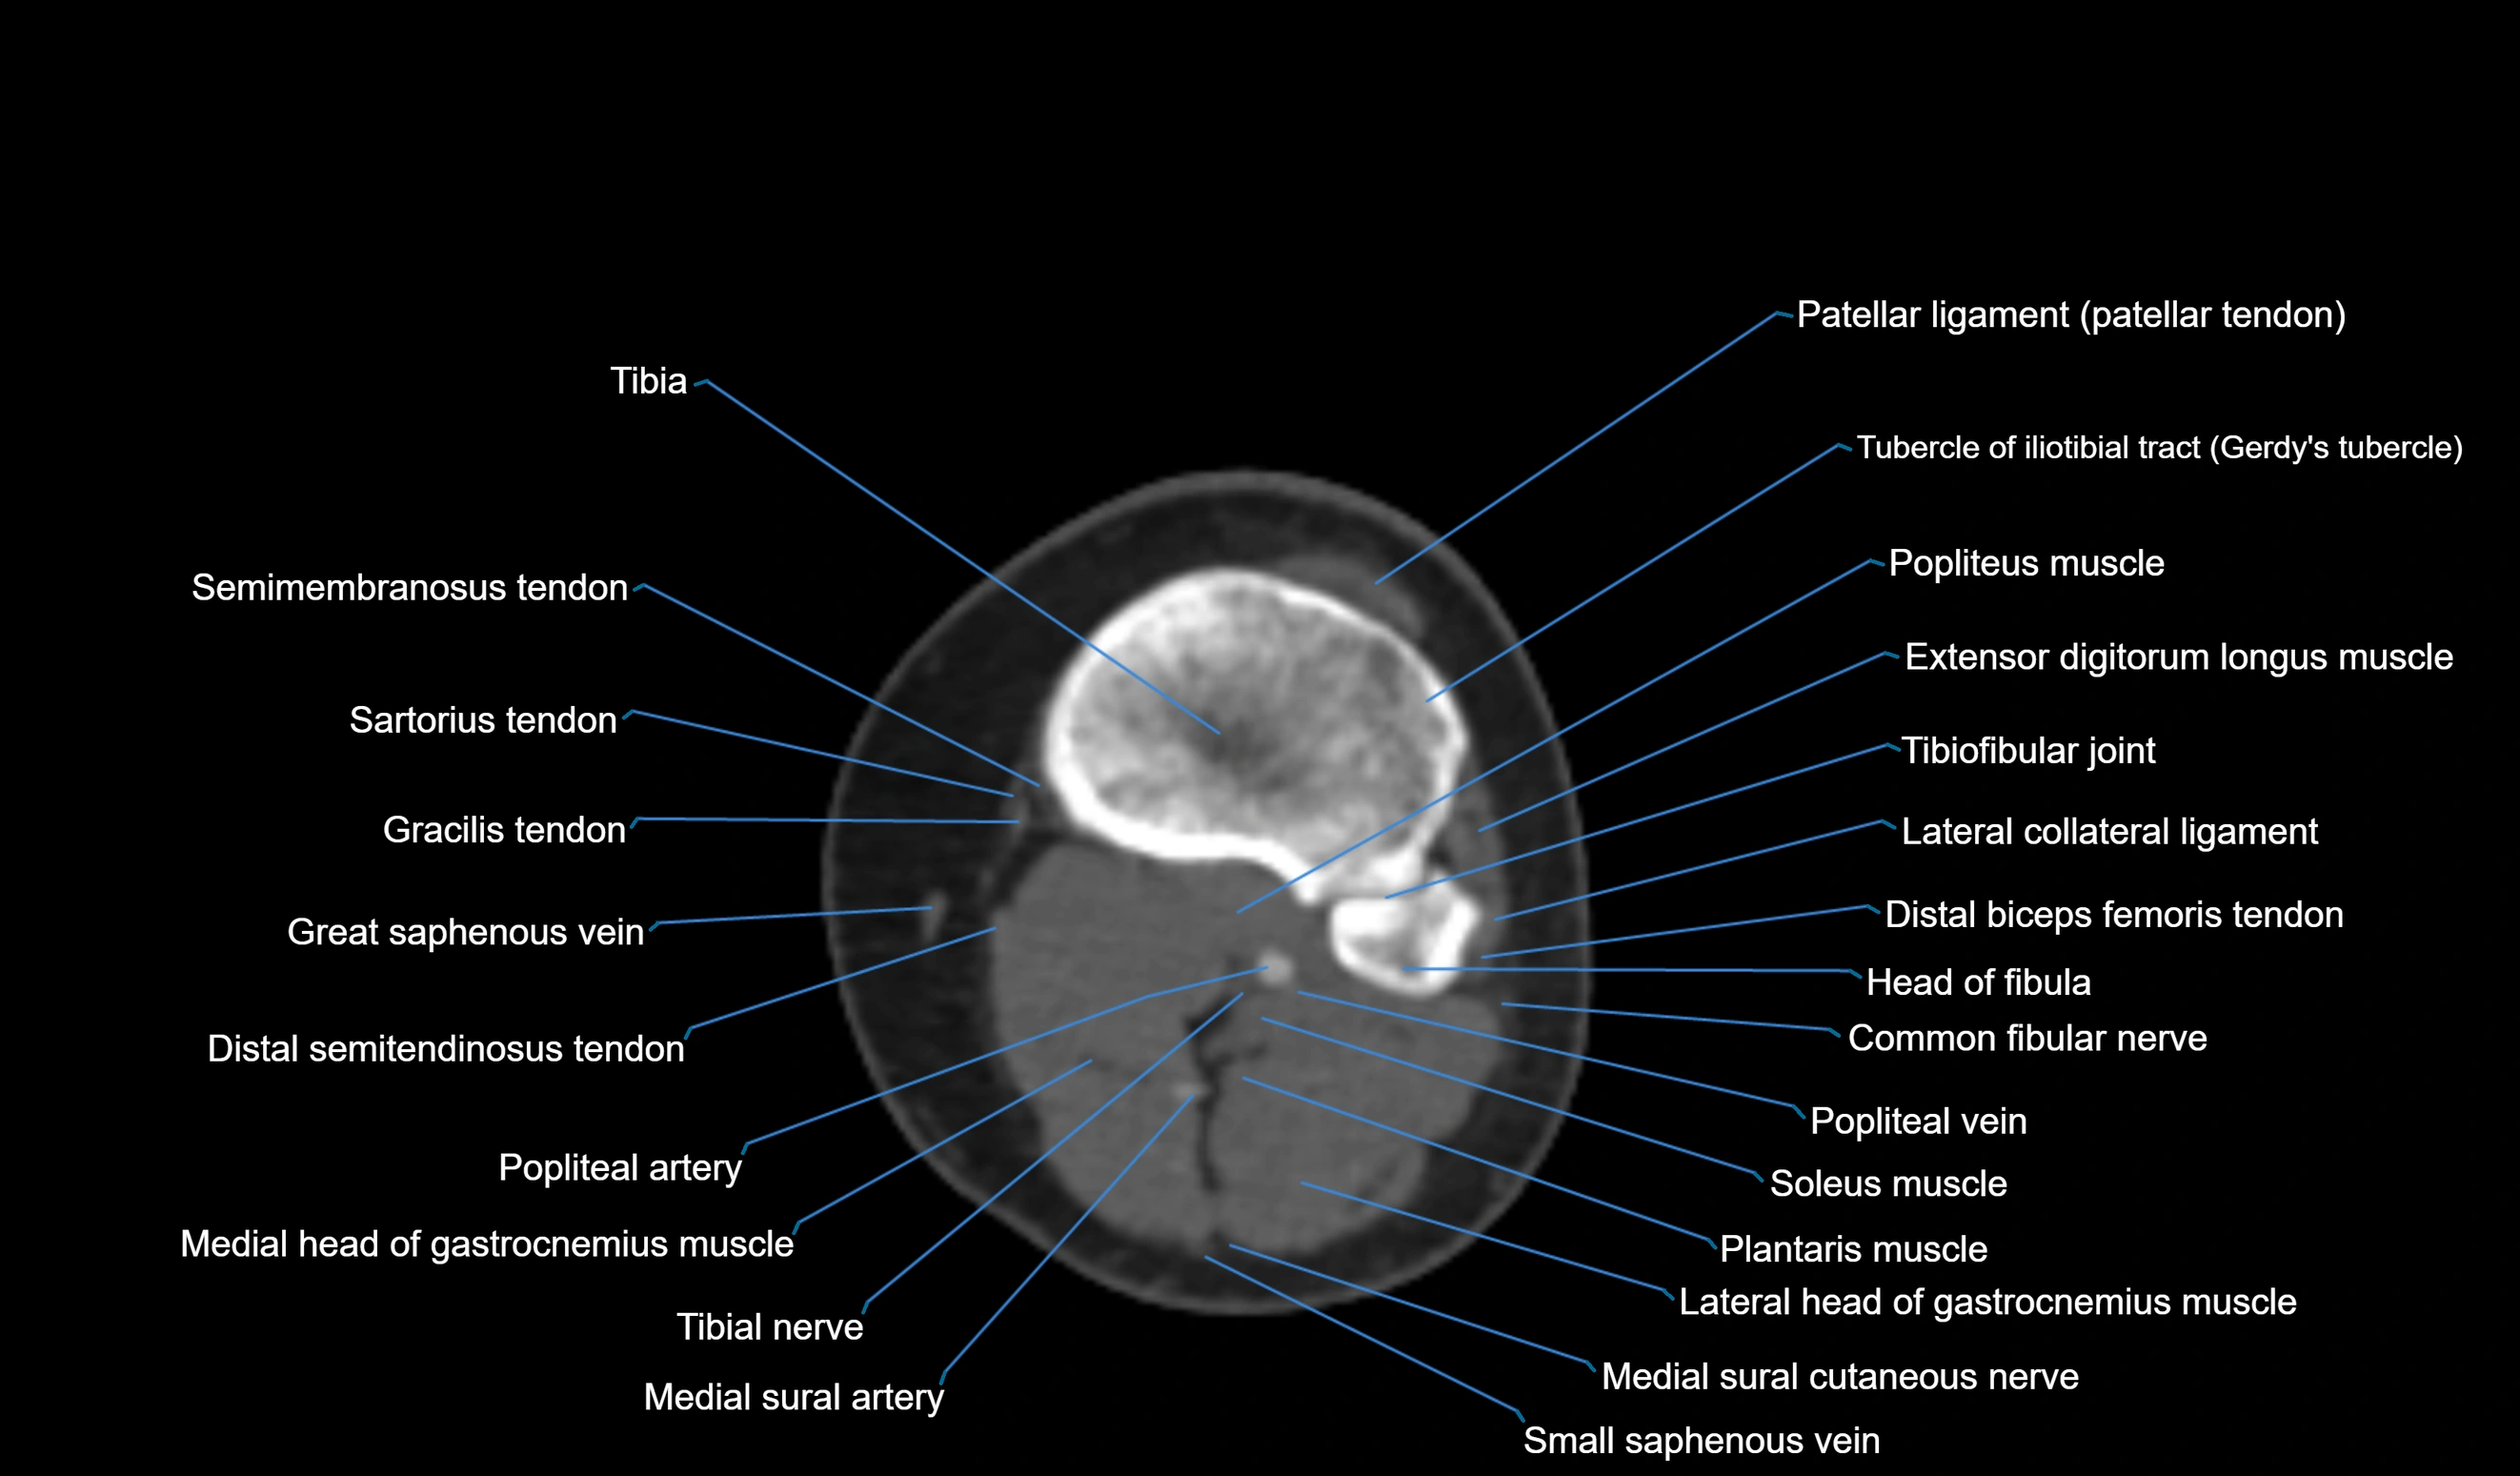

- Common fibular nerve

- Distal biceps femoris tendon

- Extensor digitorum longus muscle

- Head of fibula

- Lateral collateral ligament

- Lateral head of gastrocnemius muscle

- Medial head of gastrocnemius muscle

- Medial sural cutaneous nerve

- Patellar tendon (patellar ligament)

- Popliteal artery

- Popliteal vein

- Popliteus muscle

- Small saphenous vein

- Soleus muscle

- Tibial nerve

- Tubercle of iliotibial tract